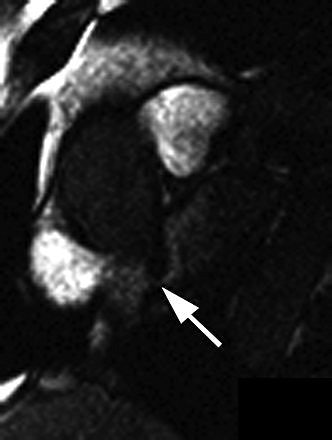

| Thirty-two-year-old man with PFO grade 3 on TEE and grade 3 on MRI. Above and below, images show enhancement of entire left atrium due to right-to-left-shunting (arrows) before enhancement of pulmonary vein. Mohrs OK, Petersen SE, Erkapic D, Rubel C, Schräder R, Nowak B, Fach WA, Kauczor HU, Voigtlaender T, "Diagnosis of Patent Foramen Ovale Using Contrast-Enhanced Dynamic MRI: A Pilot Study" (AJR 2005; 184:234-240). |

The results showed that PFO was visually identified in all 15 patients, and excluded in the control group on MRI. For the patients with PFO, "an early contrast enhancement due to intracardiac right-to-left shunting was present in the left atrium before the contrast agent reached the pulmonary veins," the authors wrote. There was a 20% prevalence of atrial septal aneurysm in the PFO population, and MRI correctly identified these cases.